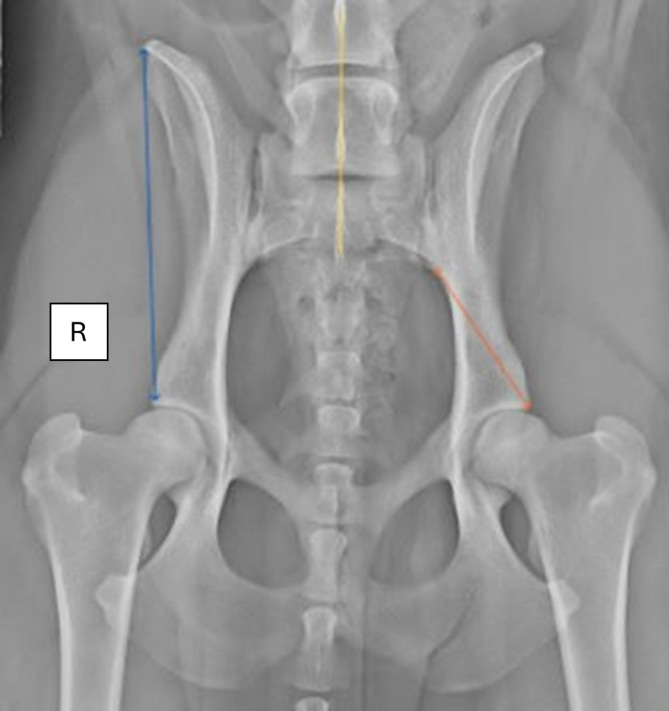

Background: A lumbosacral transitional vertebra (LTV) is a congenital anomaly of the caudal vertebral column. It has been associated with asymmetrical canine hip dysplasia (CHD) and cauda equina syndrome (CES) in German Shepherd dogs. This retrospective cross-sectional study aims to report the potential influence of asymmetric LTV on pelvic anatomy using ventrodorsal (VD) radiographs.

Results: The results are based on the evaluation of VD radiographs of 13,950 dogs from 14 breeds; an LTV was identified in 18.5%. The LTV segments were allotted into symmetrical (78.6%) and asymmetrical (21.4%) categories. An asymmetrical CHD grade was observed in 12.4% of the dogs, of which 39.7% had asymmetrical LTV. An asymmetric LTV was associated with an uneven sacroiliac joint length, in which the shortest sacroiliac joint is positioned more caudally, resulting in a reduced distance to the hip joint (P < 0.001). Rotation of the asymmetrical LTV segment about the long axis was associated with opposite pelvis rotation vertically (P < 0.001). Also, long-axis rotation of the asymmetric LTV segment was associated with an elevation of the pelvis (P < 0.001), promoting an asymmetrical CHD grade (P < 0.001).

Conclusions: This study suggests a compensatory mechanism for the sacroiliac joint related to an asymmetrical LTV. Counter-rotation between the pelvis and the LTV segment vertically may straighten the lower back. The asymmetrical LTV segment most likely affects the rotation of the pelvis and may indirectly promote an asymmetrical CHD grade.